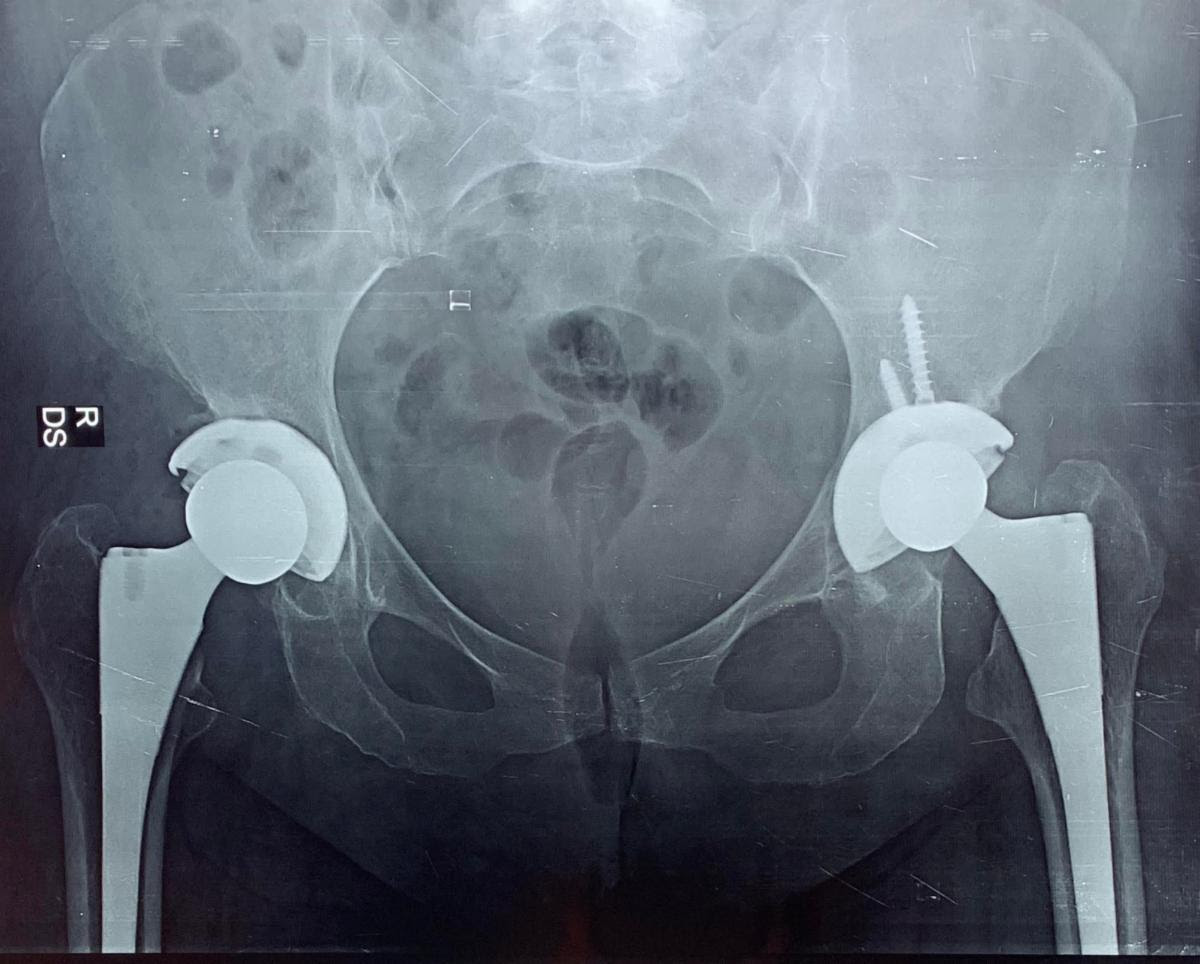

Manuja's hip before surgery.  You can see the first replacement on the right, and the hip deterioration on the left